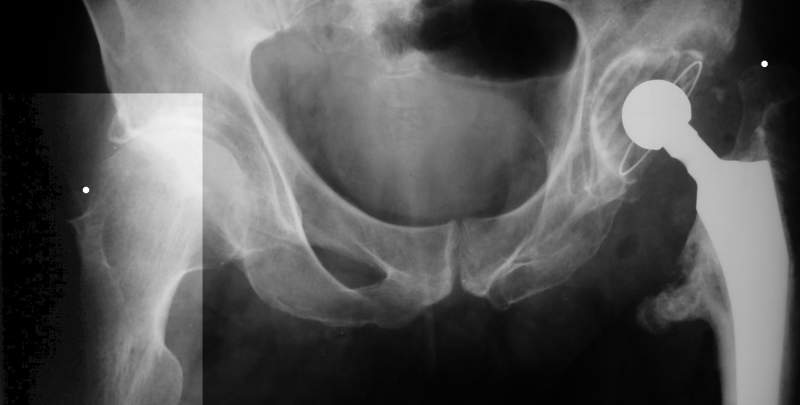

Еще пара фото, ситуация несколько иная, задачи те же, открытое вправление застарелого вывиха в 2002, молодой возраст. Сейчас госпитализирована для эндопротезирования.

--

С уважением,

Агалаков